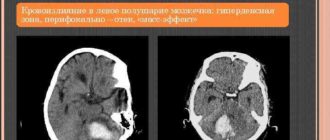

Микрокровоизлияния в левой гемисфере мозжечка

Гипоплазия мозжечка: что такое, симптоматика, как лечится Мозжечок – отдел головного мозга, регулирующий позу